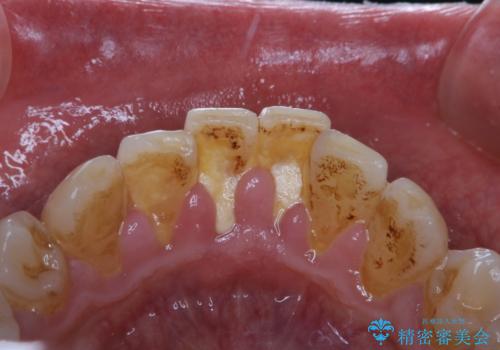

- マスクの着用により、以前より口臭が気になるとのことでした。しっかりと全体的なクリーニングを希望されたため、PMTC60分コースを行いました。

PMTCとはProfessinnal Mechanical Tooth Cleaning・専門器具による歯の機械的な清掃です。

バイオフィルム(細菌の塊)を破壊し、歯の表面をツルツルにすることでお口の中の細菌数を減らし歯周病のリスクが定着するのを防ぎます。更に、歯に新しい汚れがつきにくい状態になります。

バイオフィルムが除去されると、ご自身本来の歯の表面になります。PMTCをすることで口臭予防にもなり、定期的に行うことが大切です。